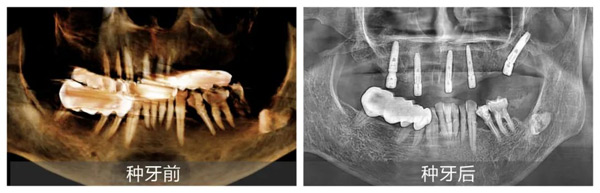

新桥口腔成都蜀汉院区种植专科主任姜辰医生接诊后,以专业严谨的态度为张叔叔进行了全面细致的检查。通过CBCT检查、口内检查及问诊,姜辰迅速判断张叔叔的牙痛是由长期牙髓炎导致牙齿腐坏,牙龈萎缩所致,牙齿已无法保留。在获取张叔叔详细体检报告并进行全面综合评估后,姜辰主任医疗团队确认其身体状况能够接受手术,果断制定了上半口即刻种植修复方案。该方案既能满足张叔叔尽快恢复咀嚼功能的需求,又最大程度地减轻了他的痛苦,缩短了治疗周期。